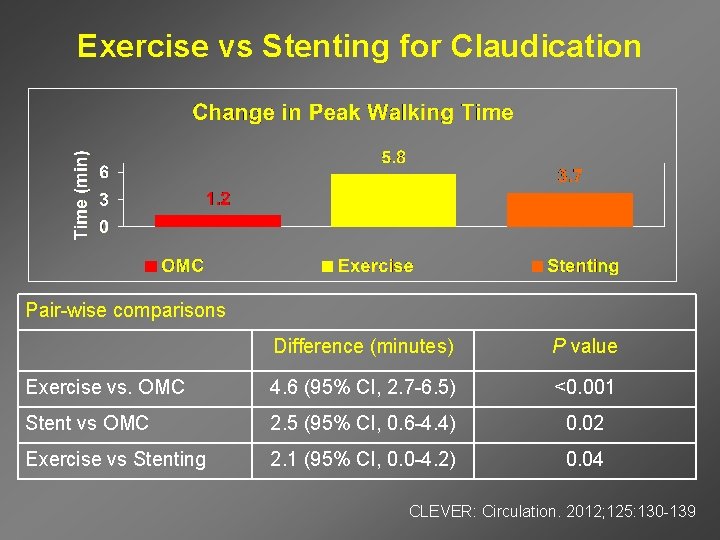

Exercise vs Stenting for Claudication Pair-wise comparisons Difference (minutes) P value Exercise vs. OMC 4. 6 (95% CI, 2. 7 -6. 5) <0. 001 Stent vs OMC 2. 5 (95% CI, 0. 6 -4. 4) 0. 02 Exercise vs Stenting 2. 1 (95% CI, 0. 0 -4. 2) 0. 04 CLEVER: Circulation. 2012; 125: 130 -139